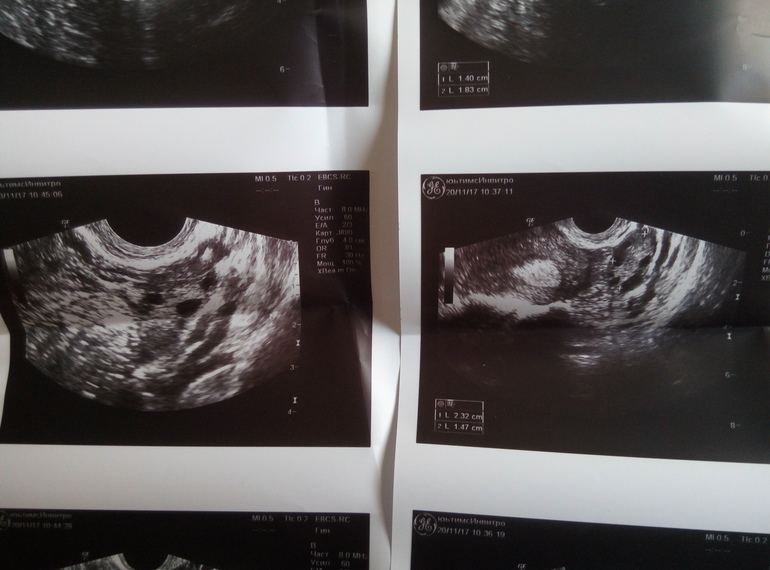

ФолликулометрияДевочки, может есть кто в узи разбирается хорошо? Что-то не понимаю как такое может быть. День цикла 22, овуляция обычно поздняя и на 17-22дц, по базальной темп О была на 15дц, заметила в этот день немного беж выделения, потом несколько дней был ЯБ, и позавчера очень резкую боль в левом яичнике(что совсем сбило с толку об овуляции), по узи: м-эхо 1,08см, форма овальная, структура однородная, контур ровный (во время узи сказала, что не очень однородной структуры) , оба яичника 6-8ф до 6мм, свободной жидкости сказала нет, но что написала в заключении- для меня загадка)) фотографию прилагаю, может кто поймет, что написано?))

Желого тела она не увидела, сказала цикл ановуляторный. Фотографии снимков тоже приложу, может кто увидит жт? :(

У кого было так, что узи не видело жт, а оно было? :(